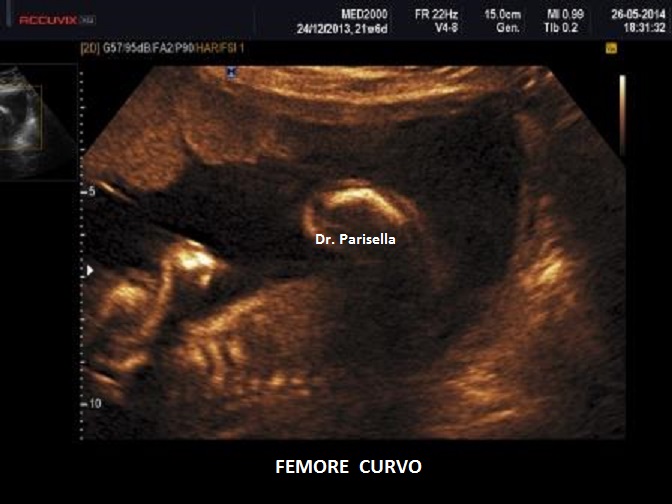

• Displasia scheletrica: ossa lunghe curve, agenesia della fibula, aspetto a ventaglio delle dita dei piedi, polidattilia;